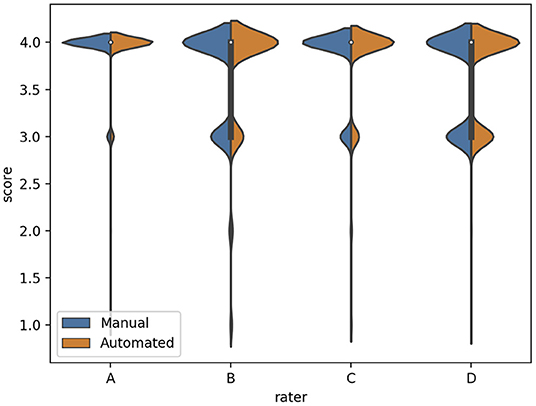

We subsequently investigated the distribution of the scores for each rater (Figure 3). We observed that the difference between the mean quality scores assigned to each segmentation method was not statistically significant for most evaluators, except for rater B (Table 1). The distribution of quality scores after excluding rater B, showed no significant difference between the two methods (OR (95% CI) = 1.05 (0.94–1.17); p = 0.40).

Figure 3. The distribution of quality scores for each rater for both sources of contours: manual (blue) and automated (orange) segmentation.

Table 1. Comparison of the mean quality score for manual and automated contours, and their corresponding Wilcoxon test p-value for statistical significance, for each rater.